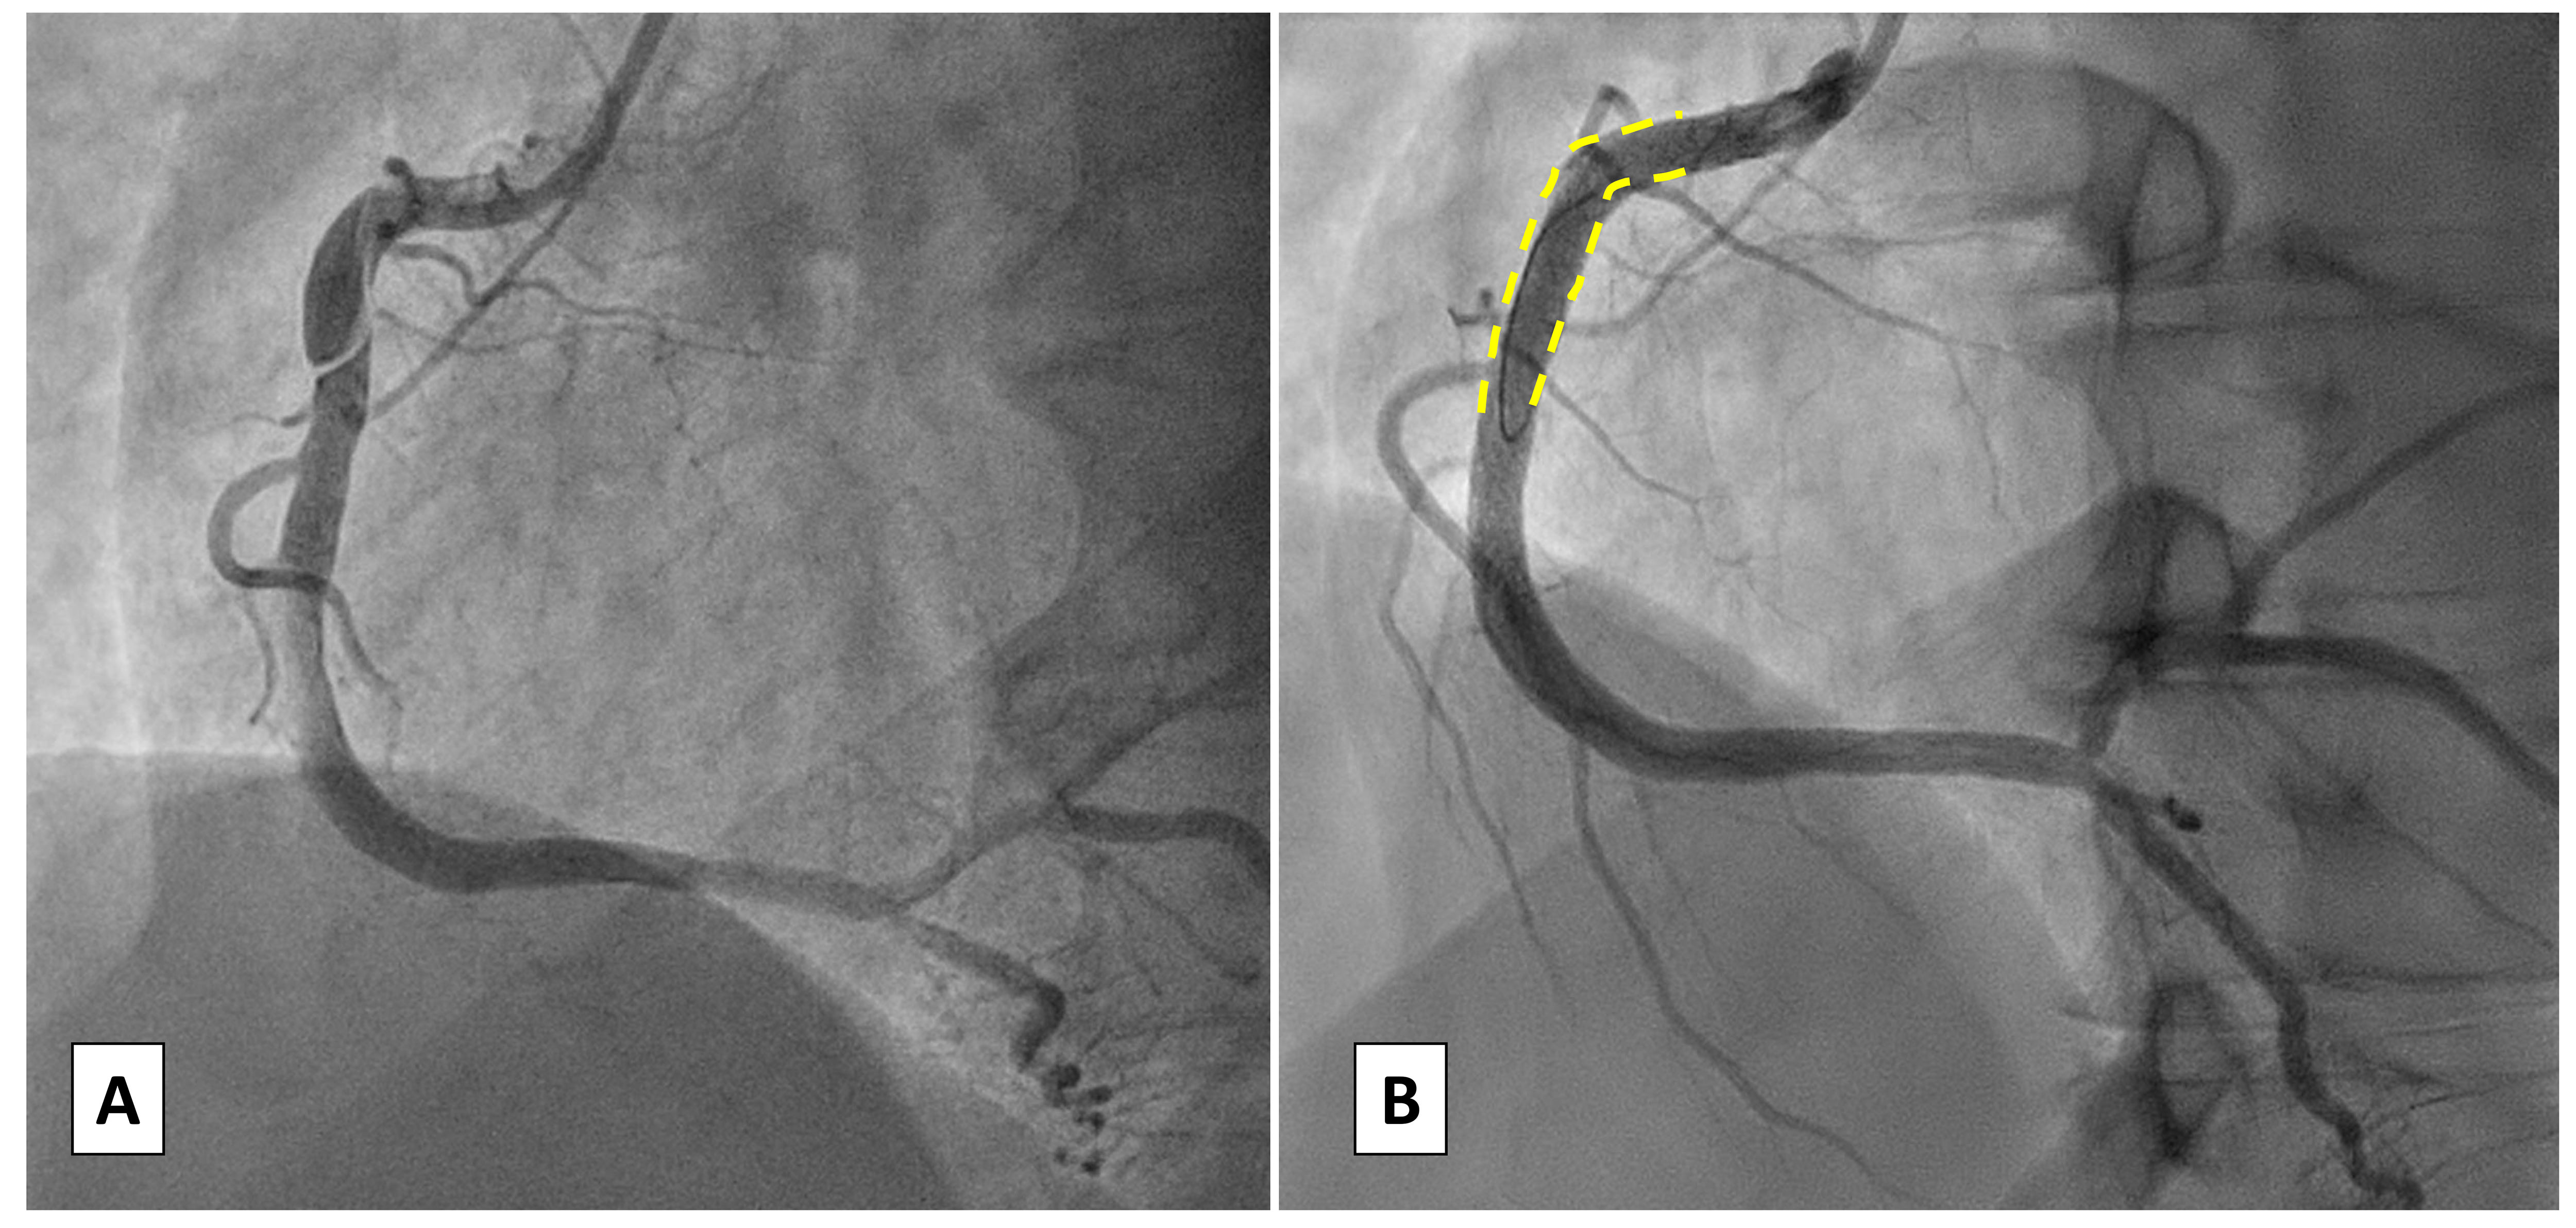

Coronary imaging (IVUS or OCT) may be exploited to verify the presence of the guidewire in the true lumen or alternatively using distal microcatheter injection only if the probability of passage into the false lumen is considered low. Imaging is relevant to improve the quality of PCI by reducing the complications but also to optimize treatment by defining the physiopathological mechanism of SCAD (i.e., “inside-out” vs “outside-in”): recent literature data in fact show that angiotypes with confined intramural hematoma given by vasa vasorum hemorrhage are more likely to worsen leading to adverse events [14], therefore an interventional strategy may be preferred. Intracoronary imaging, in particular OCT, may be hampered by difficulty in engaging true lumen, it may also cause SCAD progression and require additional contrast which increases renal damage. When multiple stent placements are necessary, a strategy involving the position of a first stent upstream to the dissection to prevent “squeezing” with retrograde extension of the hematoma may be considered, especially in case of outside-in SCAD (Fig. 4).

Fig. 4.

Case 3: Woman, 52 yo, presenting with NSTEMI, on the way to the emergency department an episode of ventricular fibrillation treated with a single direct current (DC) shock. On admission persistence of chest pain unresponsive to nitrate therapy, normal ECG and ipokinesia of the antero-lateral wall at echo: urgent coronary angiography was indicated. (A) At coronary angiography SCAD of medium and distal LAD, confirmed with intracoronary imaging using optical coherence tomography (OCT) with evidence of outside-in mechanism (absence of intimal flap). (B) Due to the clinical instability (ventricular fibrillation (VF) before admission and refractory pain) an interventional strategy was chosen: a short single drug-eluting stent (DES) was deployed to fix the proximal cap of the dissection to prevent retrograde expansion. Consecutive only balloon angioplasties were performed to break the vessel walls and empty the intramural haematoma. POBA, plain only balloon angioplasty; NSTEMI, non ST-segment elevation myocardial infarction; ECG, electrocardiogram; SCAD, spontaneous coronary artery dissection; LAD, left anterior descending artery.